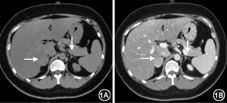

患者女,32岁。因"血压升高8个月余,血糖升高5个月余,产后11周"于2016年3月16日入院。患者孕前无心脏病、高血压、糖尿病病史,否认糖皮质激素服用史,近3年体重增加约15 kg。平素月经规律,孕前末次月经为2015年4月18日,自然受孕,孕期外院定期产检。8个月余前(孕12+周)测血压160/100 mmHg(1 mmHg=0.133 kPa),口服拉贝洛尔(100 mg,3次/d)降压,血压控制在140/100 mmHg左右。5个月余前(孕25+周)测血压176/120 mmHg,口服葡萄糖耐量试验(OGTT)示空腹、1 h、2 h血糖分别为5.59、13.45、8.71 mmol/L(妊娠期糖尿病OGTT诊断标准:空腹、1 h、2 h分别大于7.0、10.0、8.5 mmol/L);心脏彩色超声显示左心房左心室扩大,左心室射血分数42.2%;皮质醇升高且节律消失,促肾上腺皮质激素(ACTH)正常低限(表1);24h尿游离皮质醇319.15 μg/L(正常值20~80 μg/L);彩色超声示右侧肾上腺占位(约2.7 cm×2.5 cm);考虑"皮质醇增多症,腺瘤可能性大",予拉贝洛尔(3次/d)和硝苯地平控释片(拜新同,2次/d)降压、胰岛素降糖等治疗,血压控制140/90 mmHg左右,血糖控制在3.5~7.5 mmol/L。孕32+周时出现腹壁、左侧大腿内侧长条形紫纹,宽度不足1 cm。孕34+周(2015年12月24日)经剖宫产分娩1早产女活婴,体重2 480 g,身长46 cm,Apgar评分为10分,体重稳步增长。分娩后乳汁正常分泌,月经恢复;停用降糖药,血糖波动在6~10 mmol/L;监测血压,逐步调整为硝苯地平控释片30 mg(每天1~2次)降压,血压控制在140/100 mmHg左右,为进一步明确肾上腺占位性质入院。体检:心率112次/min,呼吸20次/min,血压142/90 mmHg。无多毛、痤疮、满月脸、水牛背、多血质等。心、肺检查未见异常。腹壁、左侧大腿内侧散在分布长条形紫纹,宽度小于1 cm,四肢肌力正常。入院后检查:血白细胞6.0×109/L;嗜酸性粒细胞0;尿蛋白2+;血钾4.18 mmol/L,血钠136.6 mmol/L;OGTT空腹、2 h分别为5.71、6.99 mmol/L(糖尿病诊断标准为空腹、2 h分别大于7.0、11.1 mmol/L);皮质醇水平正常但节律消失,ACTH正常低限(表1);1 mg过夜及大剂量地塞米松抑制试验均不被抑制;肾上腺增强CT示右侧肾上腺占位,双侧正常肾上腺组织萎缩(图1);心脏彩色超声示左心房左心室扩大,左心室射血分数46.8%;血及尿儿茶酚胺、肾素-血管-紧张素醛固酮正常,垂体MRI正常。诊断为"皮质醇增多症",于2016年4月20日行右侧肾上腺肿物切除术,病理符合肾上腺皮质腺瘤(图2)。术后随访3个月,停用降压药后血压波动在120~140/80~90 mmHg,皮质醇水平恢复正常(表1)。